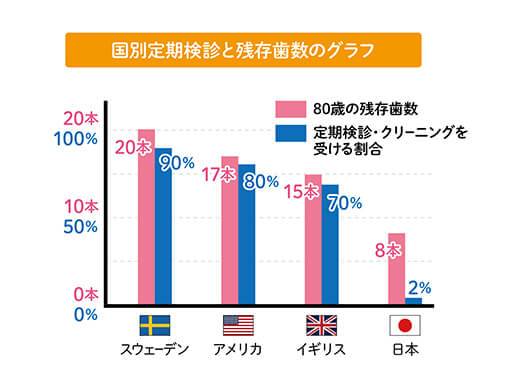

欧米では主流となっている予防歯科も、日本ではまだまだ根づいておりません。

「歯が痛くなってから」「症状が出始めてから」の治療では手遅れとなり、抜歯となる可能性もございます。

他国と比較すると日本の定期検診受診率は非常に低く、歯の残存数も圧倒的に少ないです。

ご自身の大切な歯を残すためには、定期的にメインテナンスを行い、適切なケアをすることが大切です。